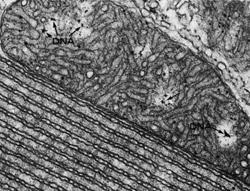

Mitochondria are structures within cells often referred to as "power houses" because they generate most of cells' energy. Unlike other cell structures, they contain their own DNA -- separate from that enclosed in the nucleus -- in the form of two to 10 small, circular chromosomes that code for 37 genes necessary for mitochondrial function. There are 10 to thousands of mitochondria per cell, depending on a cell's energy needs.

This image shows mitochondrial DNA from the snake adrenal gland, where the mitochondrion is adjacent to a highly ordered array of endoplasmic reticulum.

(Photo Credit: Image by John Long. Used with permission from 'The Cell, 2nd Ed.' by Don W. Fawcett, M.D. (Figure 227))